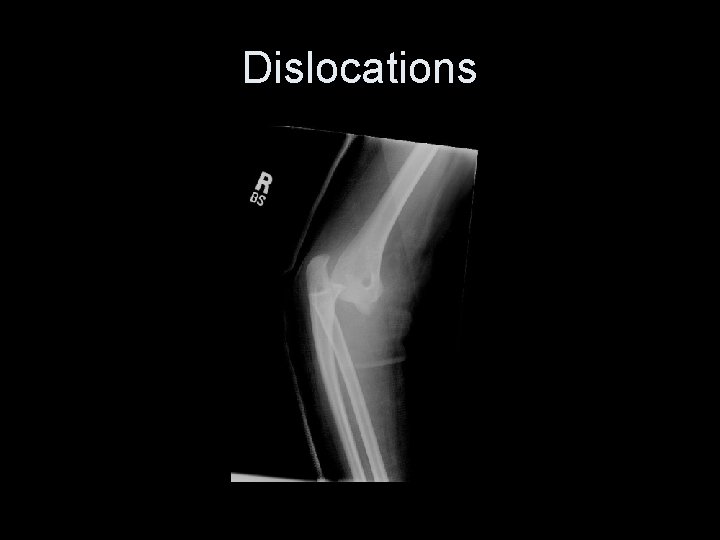

Dislocations